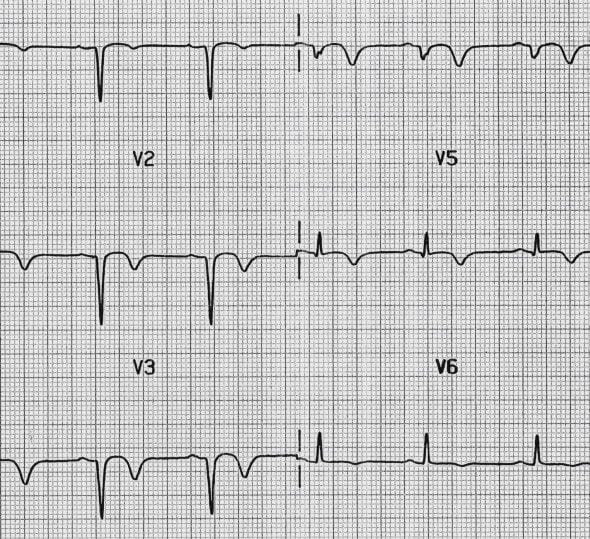

ECG Example – Inverted T wave

This ECG demonstrates inverted T waves in the precordial leads, secondary to anterior NSTEMI, pathological Q waves are also visible in leads V1-V4.

© Life in the Fast Lane. Licensed under CC BY-NC 4.0